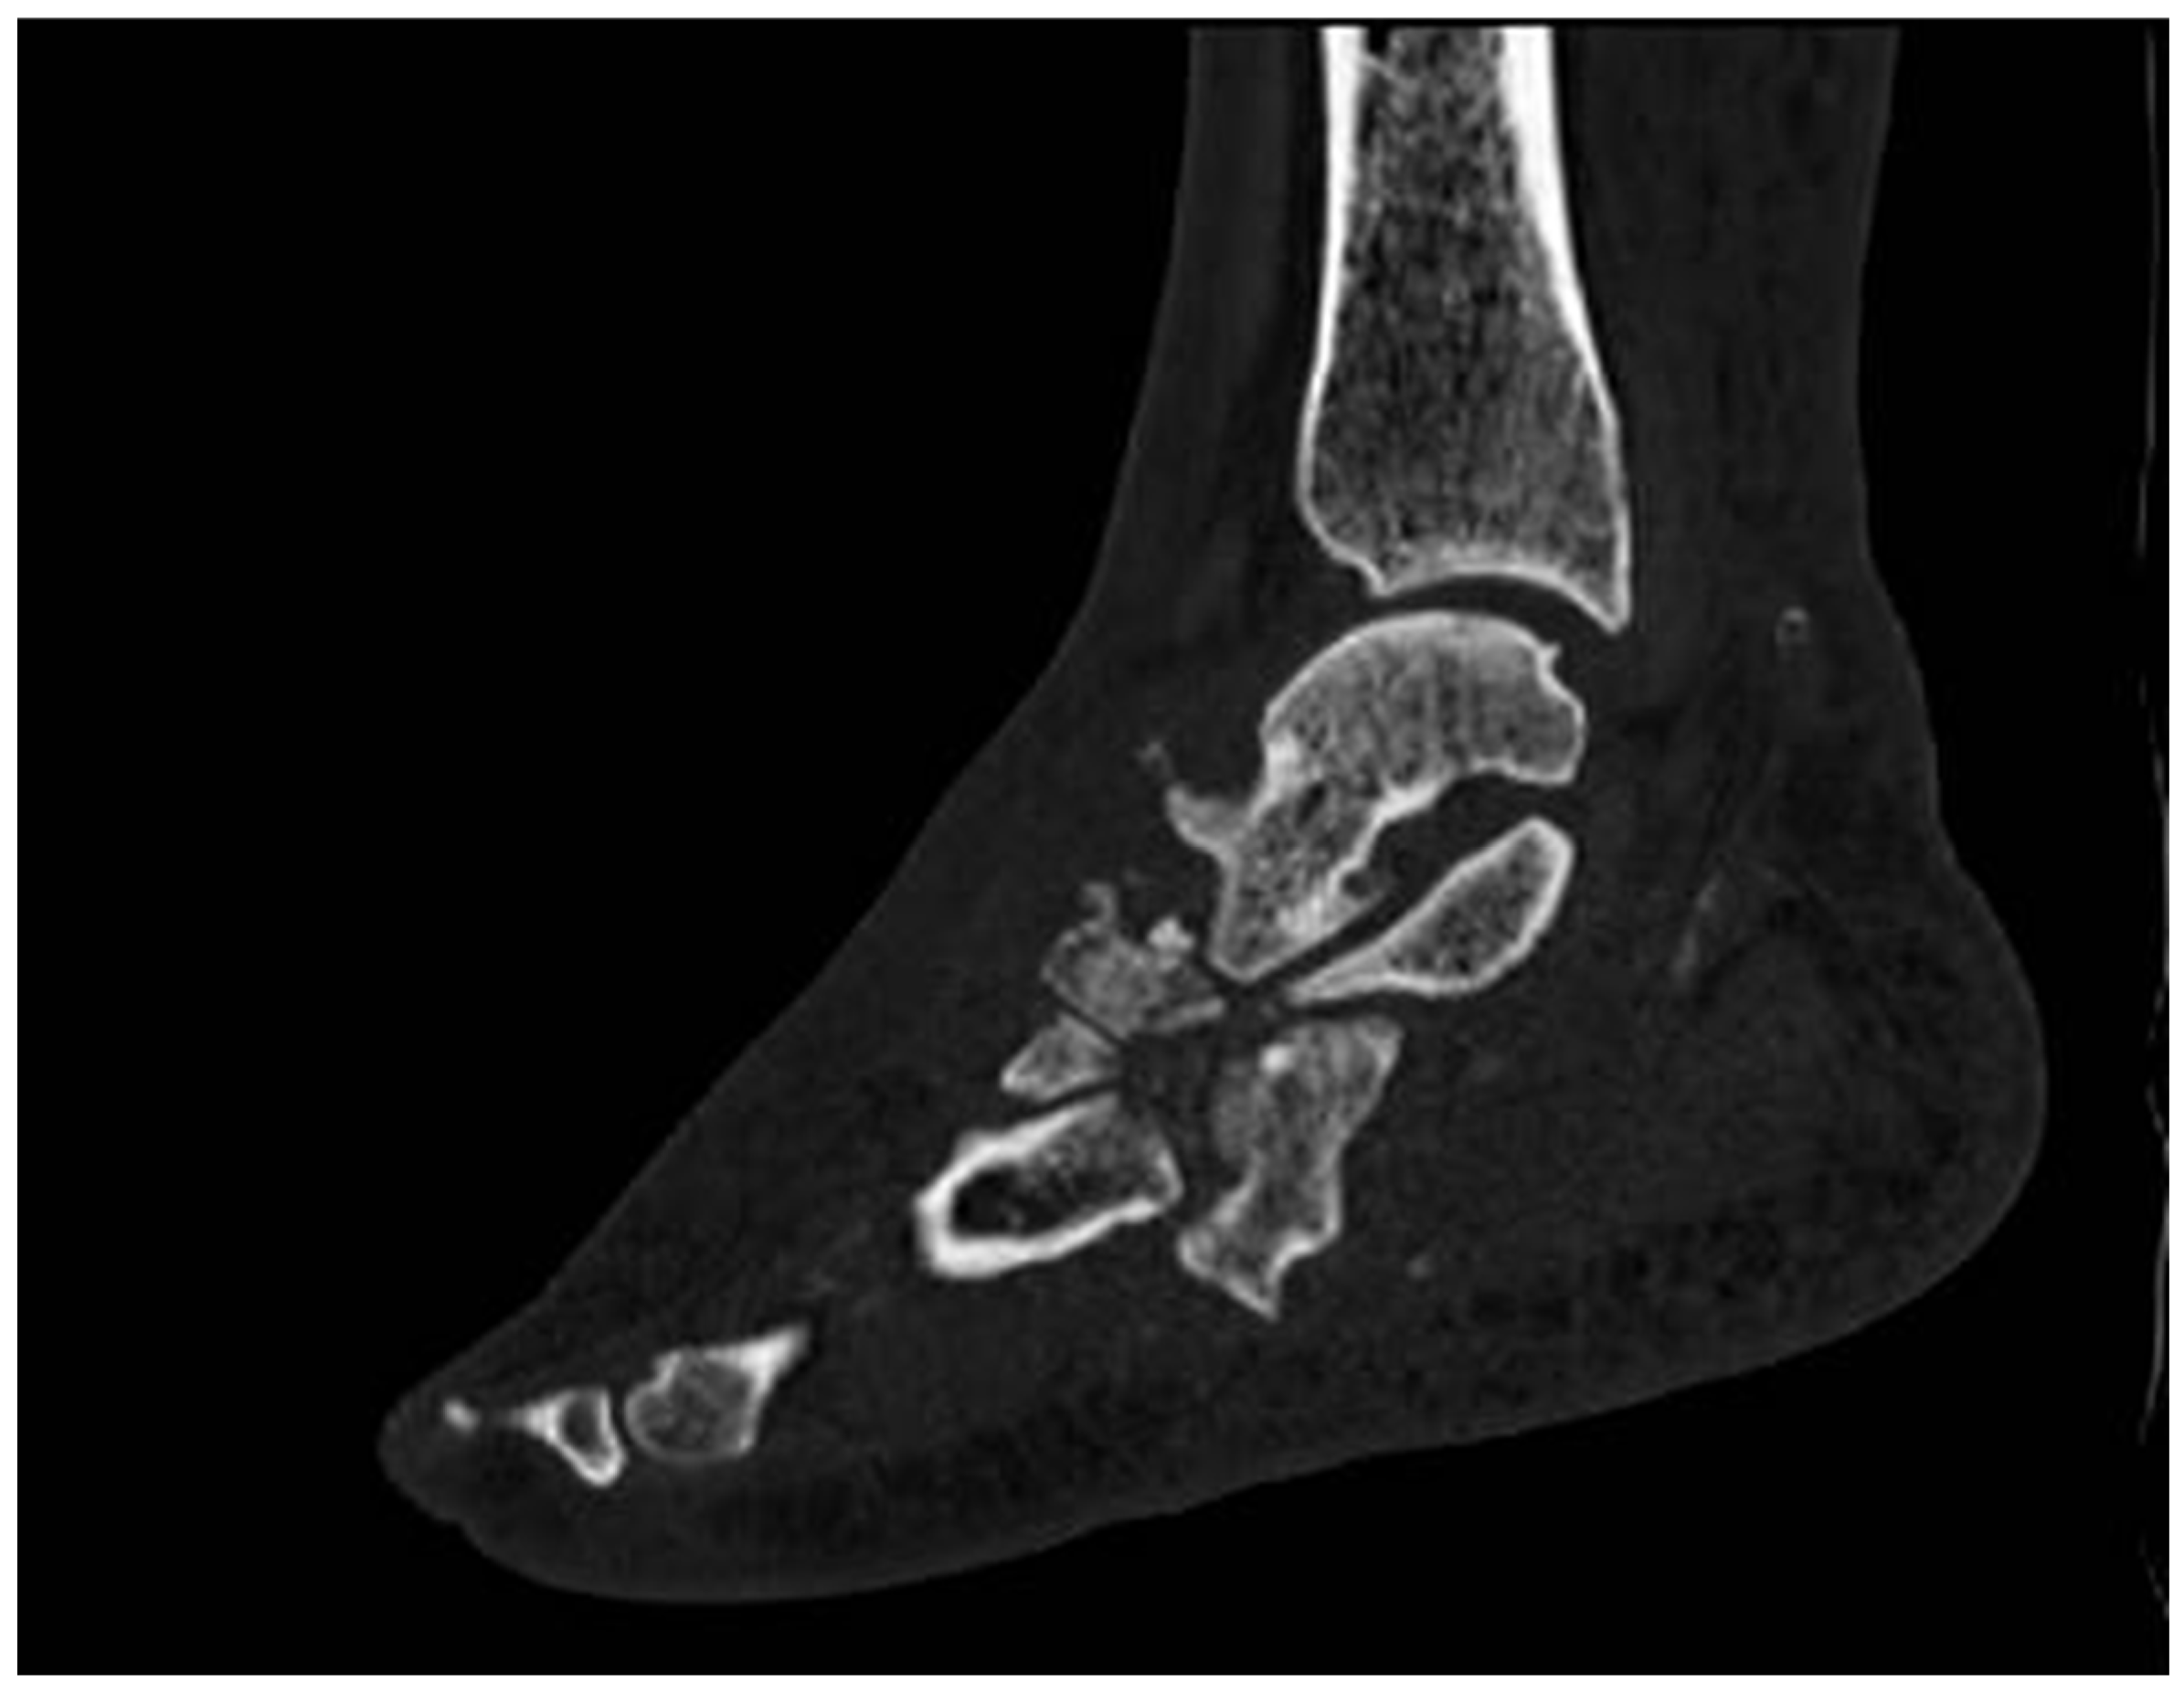

5. Computed Tomography Scan